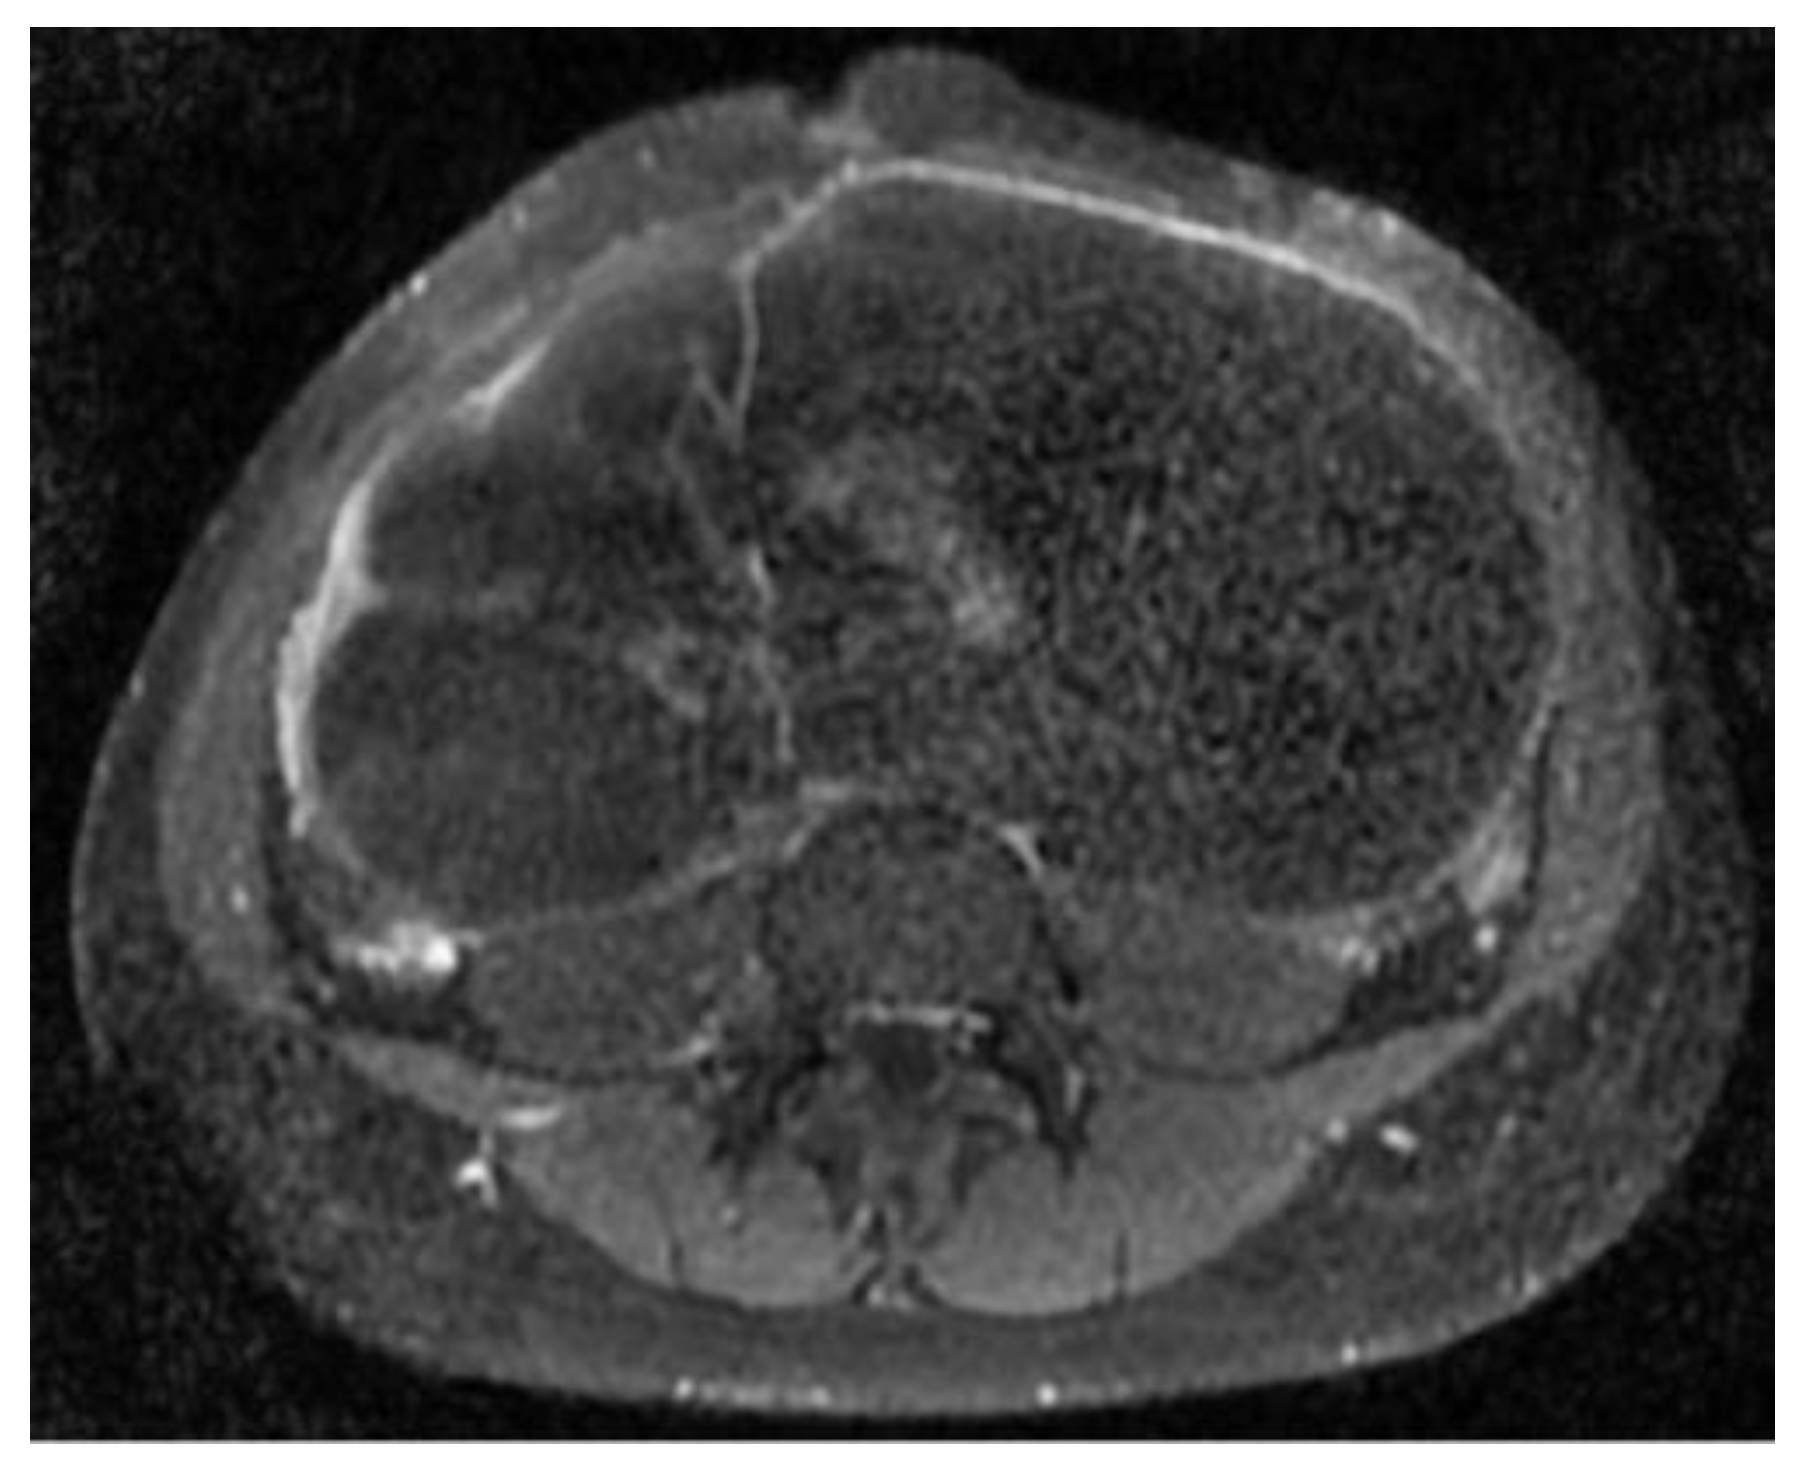

The abdomino-pelvic US showed a thin-walled, multilocular cystic mass occupying almost the entire abdomen and pelvis, with transonic content and multiple septa, some of them thick. None of the ovaries were visualized, and there was no free peritoneal fluid. Because the cyst origin could not be specified, we requested an abdomino-pelvic MRI, which showed a 115/224/350 mm cystic tumor originating in the right ovary that waswell-defined by a regular wall, multiloculated, had liquid content with some areas of high signal intensity in T1, and presented moderate mural and septal enhancement after gadolinium injection; the suggested diagnosis was ovarian cystadenoma (Figure 2 and Figure 3).

Figure 3. Axial postcontrast T1 sequence shows a cystic mass with moderate mural and septate contrast enhancement.